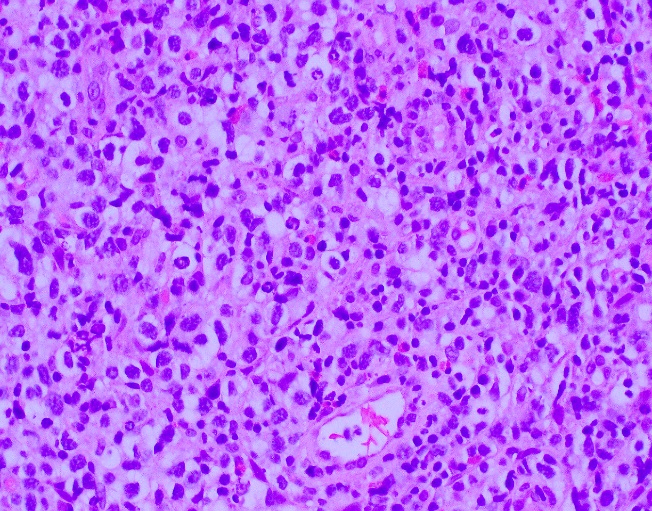

The core needle biopsy material demonstrated a lymphoid population that was polymorphic in appearance with medium to large sized lymphocytes with moderate amounts of pale cytoplasm, irregular nuclei, vesicular chromatin, and some cells with prominent nucleoli. The background cellular population is composed of a mixed inflammatory component including small lymphocytes, scattered neutrophils, eosinophils, and histiocytes.

By immunohistochemistry, the medium to large sized cells with pale cytoplasm are positive for CD3, CD2, CD4, and CD5 with complete loss of CD7. CD20 highlights scattered background B-cells. CD21 is positive in disrupted follicular dendritic meshworks. CD10 and BCL6 are negative in neoplastic cells. PD1 is positive in neoplastic cells with a subset co-expressing CXCL13. By Ki-67 immunostaining, the proliferation index is 50-70%. By in situ hybridization for Epstein-Barr virus encoded RNA, a subset of cells are positive.

Overall, with the morphologic and immunophenotypic features present, the diagnosis is that of angioimmunoblastic T-cell lymphoma.